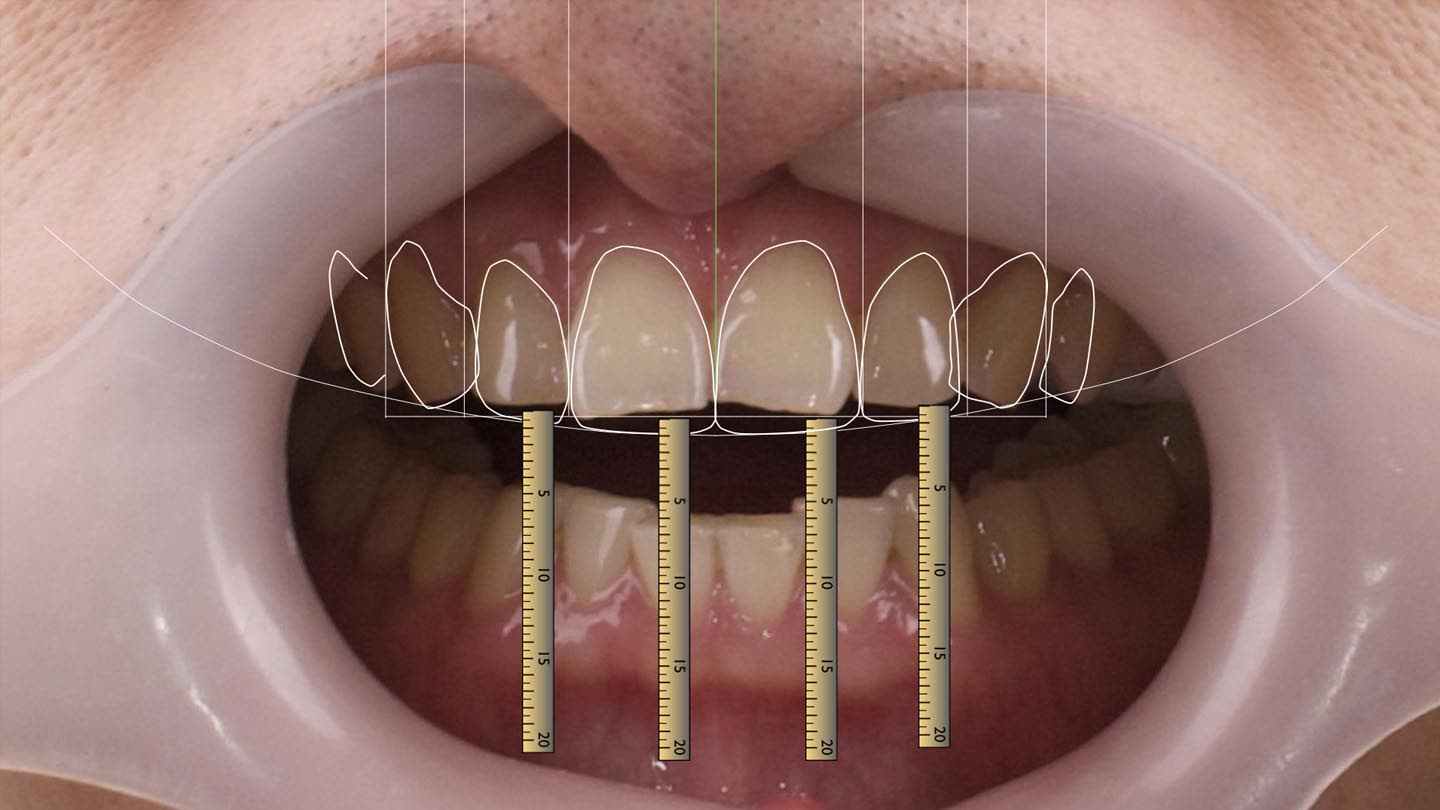

Following confirmation of complete neuromuscular deprogramming by achieving a repeatable spot on the deprogrammer platform, a definitive maxillomandibular relationship record was obtained. Comprehensive records required for digital smile design (DSD) were collected and evaluated (Figure 7). These included the following photographic views in fixed head position: three frontal views: full face with a wide smile and teeth apart, full face at rest, and retracted view of the full maxillary and mandibular arches with teeth apart; two profile views: side profile at rest and side profile with a full smile; 12 o’clock view with a wide smile and incisal edges of the maxillary teeth visible and resting on the lower lip; and an intraocclusal view of the maxillary arch from second premolar to second premolar.7

The maxillary cast was mounted using a Kois dentofacial analyzer, while the mandibular cast was mounted in centric relation based on the recorded jaw position. The articulated casts were subsequently forwarded to the dental laboratory for fabrication of a diagnostic wax-up incorporating the planned occlusal and esthetic modifications.

After clinical approval of the wax-up, the laboratory duplicated both the maxillary and mandibular casts. On the duplicated casts, every other tooth was selectively reduced back to its original anatomy. This approach enabled fabrication of two transparent injection matrices per arch, allowing for an alternating injection sequence (Figure 8 through Figure 10).8